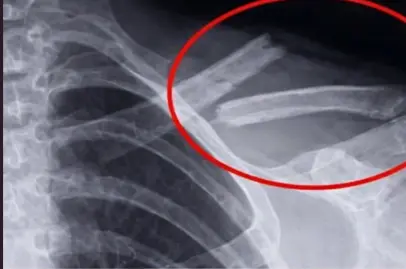

- 🩻 Maior risco de fraturas

um simples tombo resulta em uma fratura grave.

Muitos só descobrem quando fazem exames ou após um acidente inesperado.